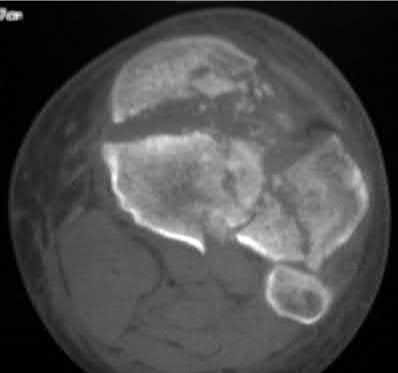

Question 19

A 28-year-old male sustains a closed comminuted tibial shaft fracture.

Two hours post-injury, he develops severe leg pain unyielding to narcotics. His blood pressure is 120/80 mmHg. Intracompartmental pressure monitoring is performed. Based on current guidelines, which measurement dictates an emergent 4-compartment fasciotomy?

Explanation

Acute compartment syndrome is classically defined by tissue hypoperfusion. The absolute compartment pressure is less reliable than the differential pressure (Delta P). A Delta P (Diastolic Blood Pressure minus Compartment Pressure) of less than 30 mmHg is an absolute indication for emergency fasciotomy, as capillary perfusion gradient is lost when tissue pressure approaches the diastolic pressure.